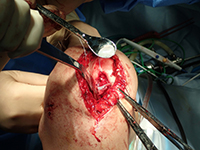

自家培養軟骨移植術 関節鏡下自家骨軟骨柱移植術

培養軟骨移植の術前術後写真